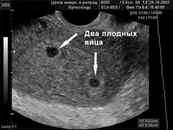

Диагностика на ранних сроках: Современные методы ультразвукового исследования позволяют выявить многоплодную беременность уже на ранних сроках — обычно на 6-8 неделе. При этом врачи могут не только подтвердить наличие нескольких эмбрионов, но и оценить их развитие и состояние.

Диагностика многоплодной беременности обычно осуществляется с помощью ультразвукового исследования (УЗИ), которое позволяет визуализировать количество плодов. Обычно первое УЗИ проводится на сроке 6-8 недель, и в большинстве случаев уже на этом этапе можно определить, сколько эмбрионов развивается в матке.